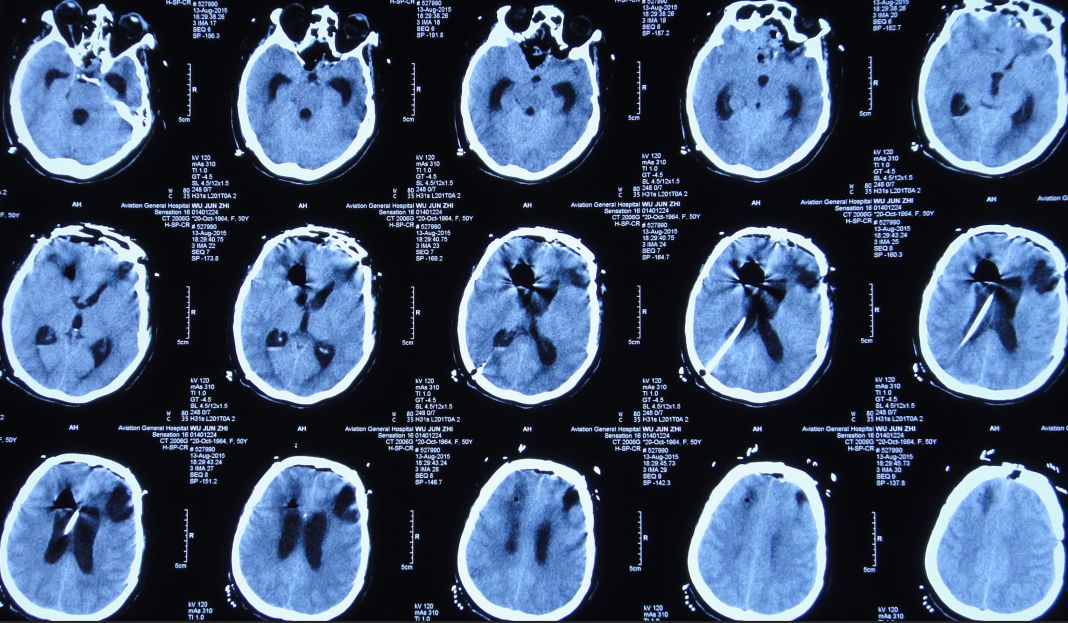

2015年7月27日患者突发高热,体温高达39.0 ℃,伴呕吐,意识转差,腰椎穿刺颅内压力极高,并留取脑脊液进行细菌培养;复查头CT检查显示脑室系统显著扩张,颅内积气(图11)。当日急诊进行了右侧侧脑室钻孔引流术,术后入住ICU给予重症监护、抗炎、抑酸等治疗。

图11:2015年7月27日头CT:脑室系统显著扩张,颅内积气